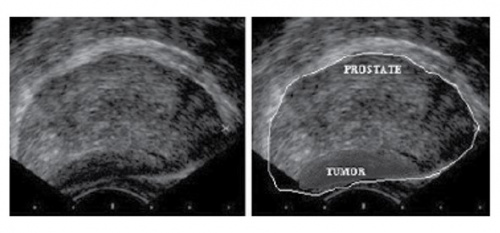

4. 전립선암(Prostate cancer) 소견

• 전립선암은 대부분 주변구역에서 생긴다.

• 전립선암의 약 60-70%에서 정상적인 주변구역에 비해 저에코를 보인다.

- 하지만 40% 정도는 정상 주변구역과 비교하여 동등한 에코를 보이므로 저에코라고 전립선암으로 단정하기도 어렵다(양성예측도 18~52%).

• 저에코 병변은 직장수지검사 등으로 경도를 측정해보는 것이 특이도를 높일 수 있는 방법이다.

• 전립선 피막의 비틀림이나 불연속성은 진행된 전립선암의 중요한 진단 요소이다.

• 전립선암 병소로 인해 전립선 모양의 비대칭성을 관찰할 수 있다.